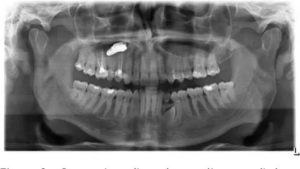

Только на рентген снимке или на экране компьютера при томографии можно обнаружить проблему.

- рентген снимок, который показывает не только наличие тела, но и пневматизацию (наличие воздуха);

- Рентгенография верхнечелюстных пазух – на снимках отлично видны все уплотнения, гнойные образования и другие дефекты.В данном случае понадобится также диагностика и консультация врача-хирурга, комплексный осмотр поможет выявить проблему и назначить лечение.

Наверняка каждый человек лечил зубы, и часто лечение сопровождается пломбировкой каналов зуба. Дело в том, что корни верхних зубов особенно 5 и 6-го часто вдаются в верхнечелюстную пазуху и прикрыты со стороны пазухи только слизистой оболочкой.

Таким образом, стоматолог, совершенно без злого умысла, проводя работу над корнем зуба, может проткнуть ее верхушку и протолкнуть пломбировочный материал в пазуху. Более того, иногда в пазуху может попасть даже фрагмент самого корня зуба или корень полностью. Вот тут и начинается самое интересное.

Практически в 100% случаев точно диагноз позволяет установить КОМПЬЮТЕРНАЯ томография пазух носа. Обычный рентген и МРТ дают менее информативную картину. На результатах компьютерной томографии часто можно четко увидеть и пломбу и формирующееся грибковое тело, как показано на рисунке.

Пациенты могут испытывать небольшой дискомфорт в области верхней челюсти, иногда возникает гнойный гайморит на стороне грибкового тела. И, естественно, в прошлом пациенты лечили у стоматолога верхние зубы. К сожалению, других характерных симптомом болезни просто нет.